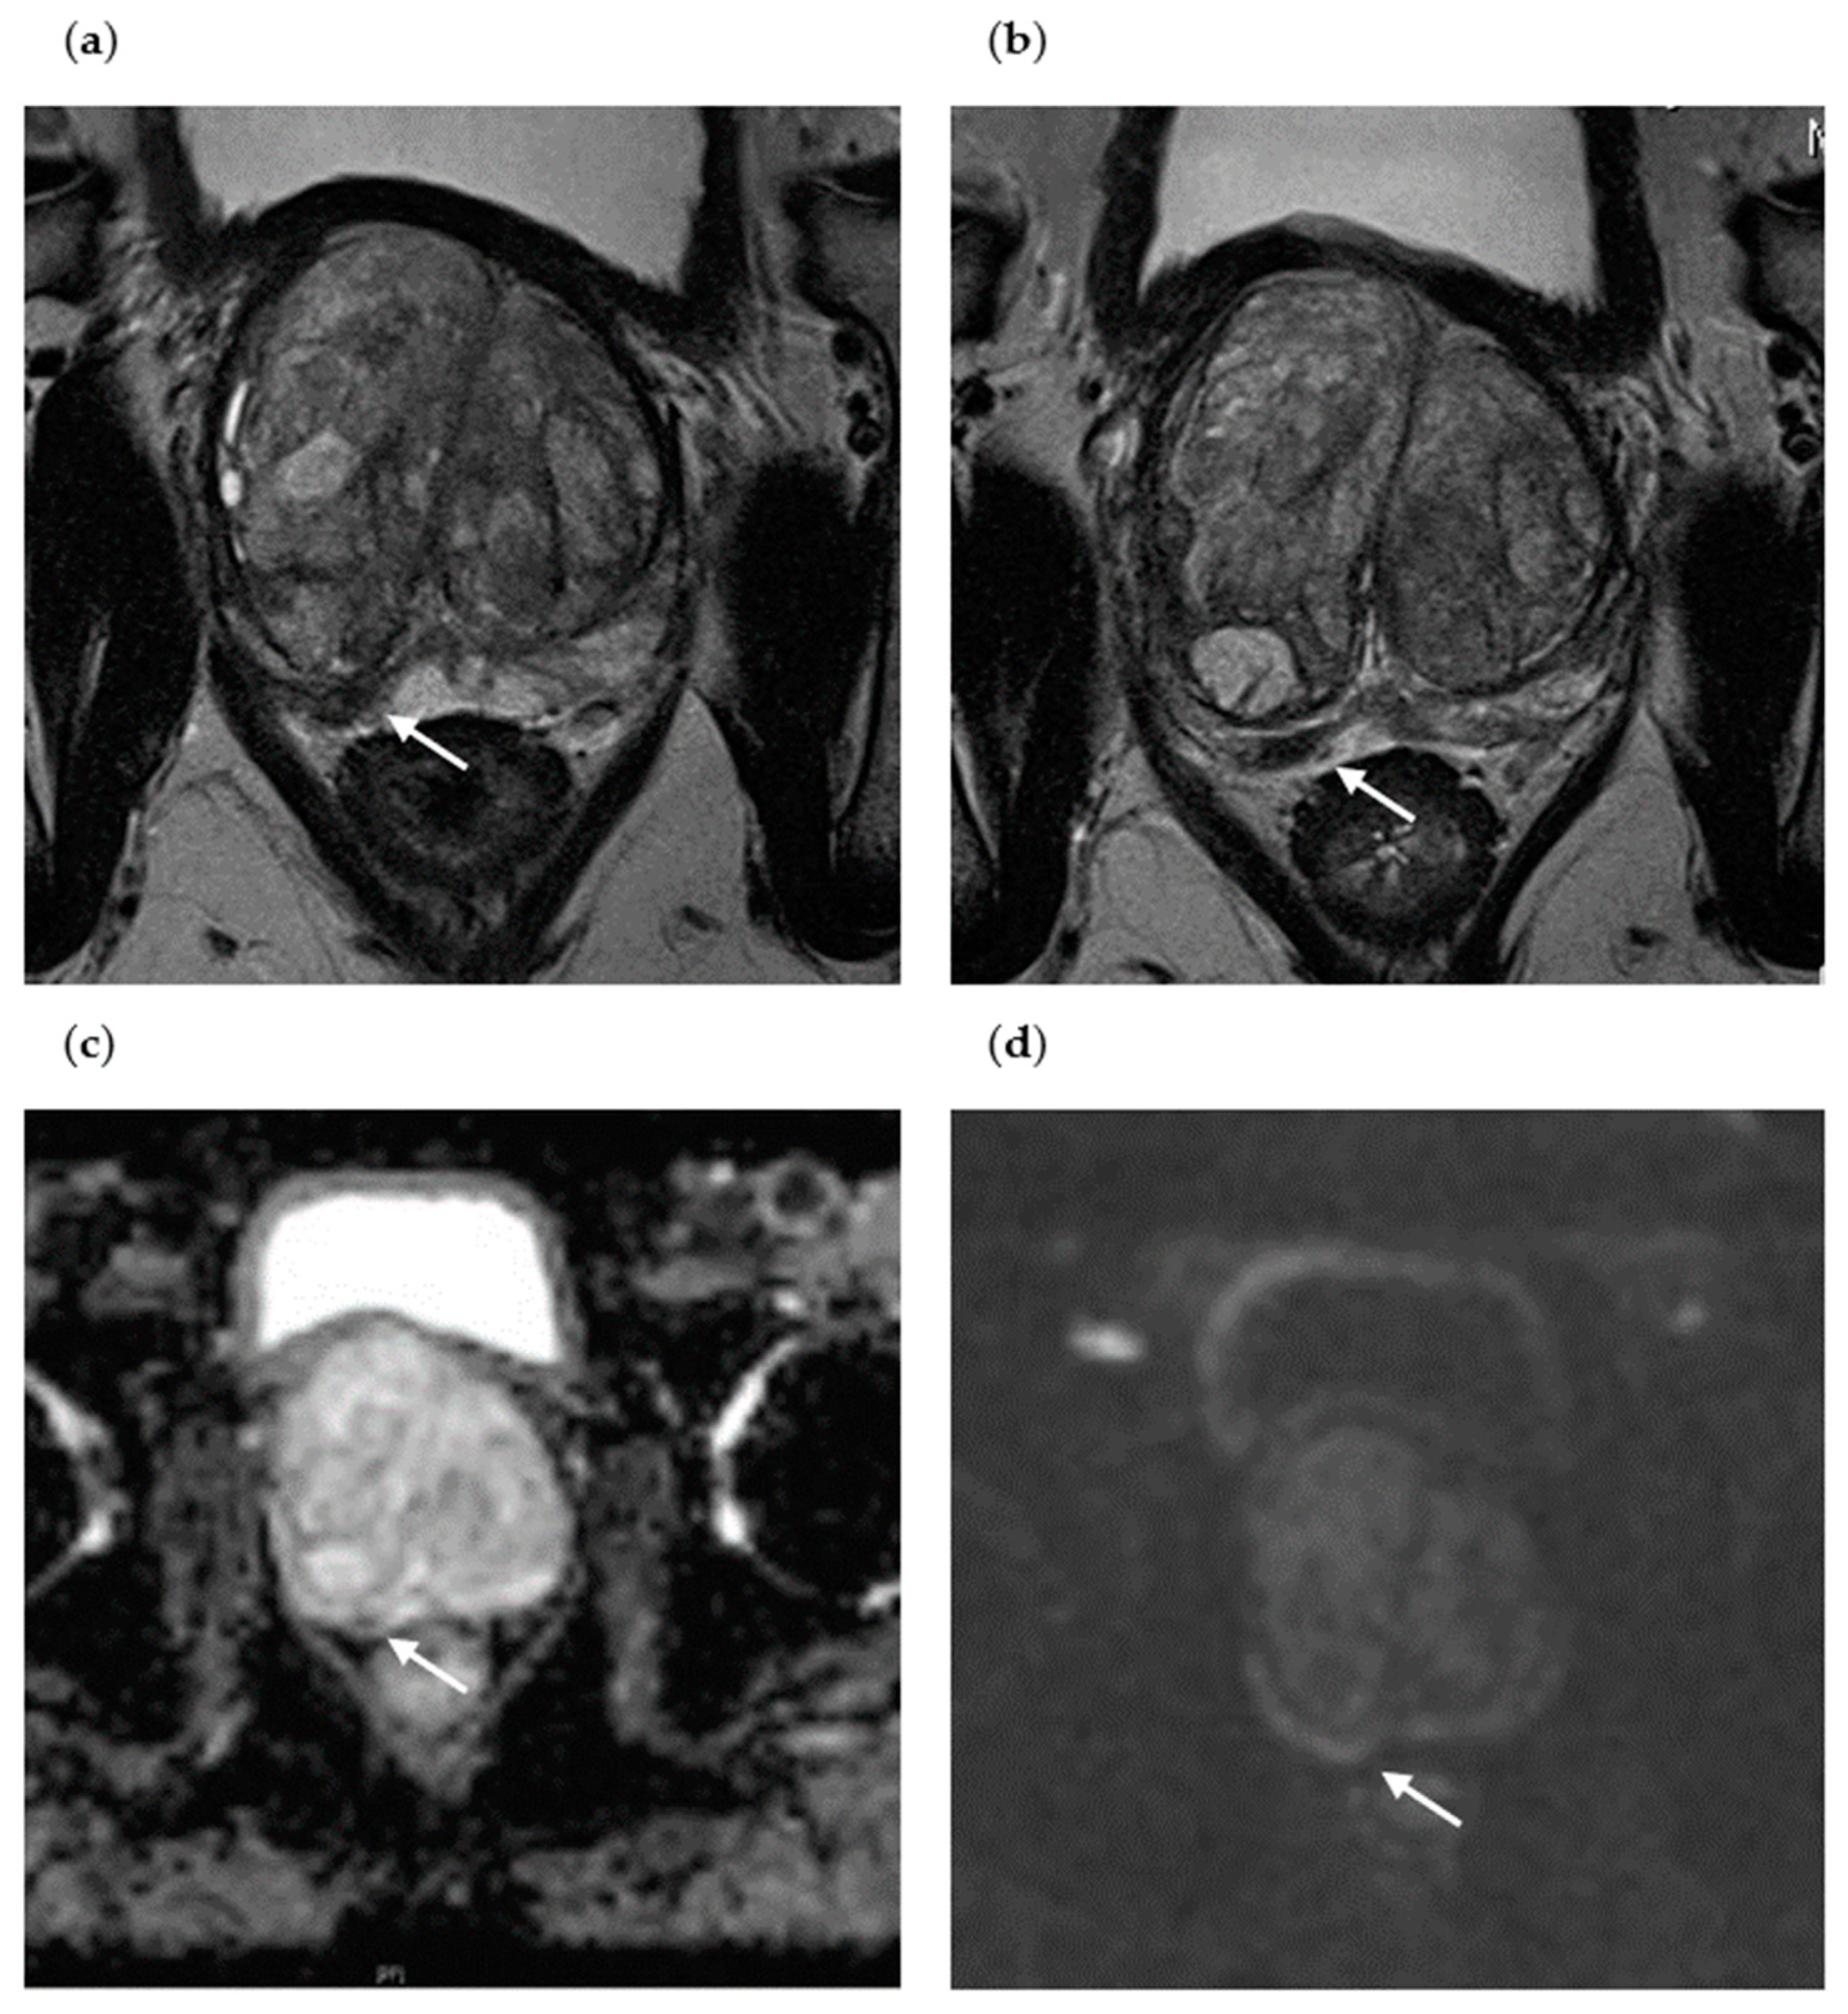

3.3. Initial and Follow-Up mpMRI of Two Patients with sPC Detection at Repeat Biopsy

3.4. Initial and Follow-Up mpMRI of Two Patients without PC Detection at Repeat Biopsy